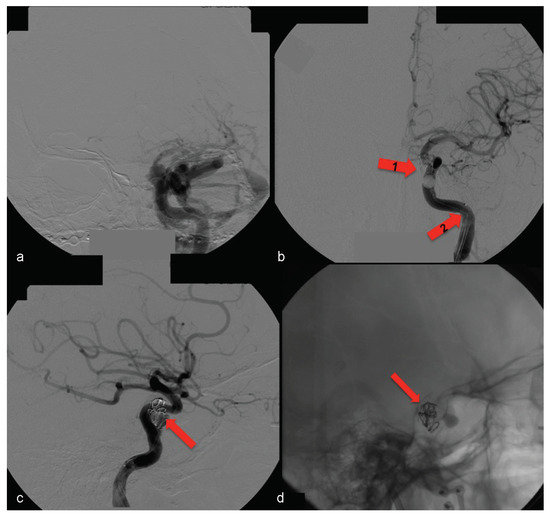

Examination of the patient showed normal results on the right side (Figure 7). The left side displayed significant alterations (Figure 8). It showed Type A CCF.

In this case, the right femoral artery was punctured for the bilateral carotid and vertebral angiography. Type A CCF was treated by embolization of the left traumatic cavernous aneurism using a Tracker Excel 14 microcatheter (Boston Scientific Corporation, Neurovascular Division, Freemont, CA) and a TS 14 microguide (Micro Therapeutics, Irvine, CA) to selectively catheterize the CS on the left side, by depositing nine detachable GDC microcoils (Boston Scientific Corporation) associated with a detachable balloon (Figure 9) inside it.

Figure 9.

(a) Left side angiography, with coronal view, showing congestion toward the left orbit. (b) The same coronal view with occluded fistula— arrow no. 1 highlights the activated balloon and arrow no. 2 highlights the microcatheter. (c, d) Left side angiography, with sagittal view showing the detachable microcoils used for permanent carotid-cavernous fistula occlusion (arrows).